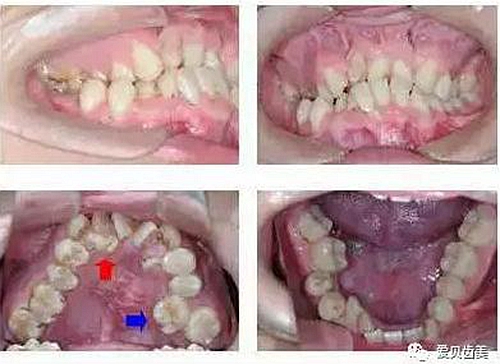

4.jpg

特別提醒:牙列擁擠不僅會(huì)反過來增加牙齒清潔難度,還會(huì)增加牙菌斑、蟲牙的發(fā)生。好了,今天就和大家分享到這里吧,早期發(fā)現(xiàn)就會(huì)少些煩惱,早期了解就順便說一下啊,成人這樣的情況也不少,除及時(shí)看診之外,我們還要注意平常的合理飲食。